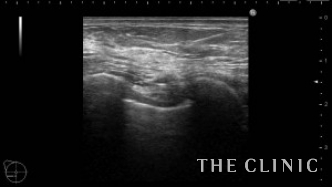

No.23でご紹介した方のオイルシストです。

エコー下にて穿刺吸引を行いました。